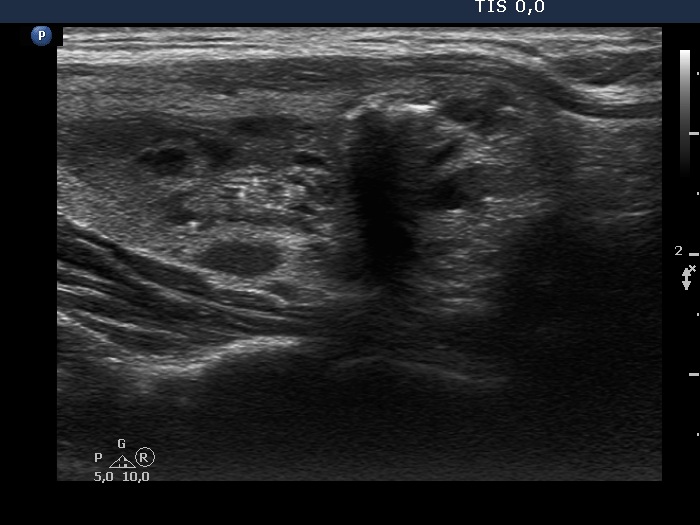

Ultrasonography. The thyroid was echonormal. There were two nodules in the right lobe, a dominantly cystic one, and a lesion in the lower third which had macrocalcifications. There was a minimally hypoechoic lesion in the left lobe which showed halo sign and perinodular vascularity. Compared with the first examination, the nodule in the left lobe showed a substantial increase, this time the dimensions were 15x14x17 mm.

The ultrasound presentation of the left lobe is almost diagnostic of follicular tumor, a solitary, homogeneous lesion presenting halo and perinodular blood flow has more than 90% risk being a follicular tumor.